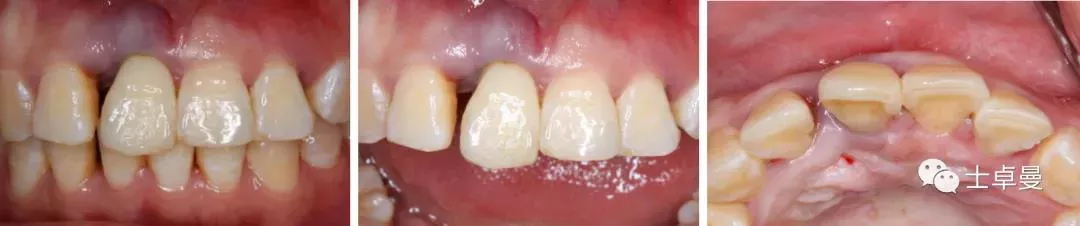

·      ▷ 就诊时检查口内检查

·      11伸长,牙龈呈紫红色,BOP(+),松(Ⅲ);

·      12松(Ⅰ-Ⅱ),21松(Ⅰ-Ⅱ),22松(Ⅱ);

·      牙龈未见明显炎症,余留牙未见异常;

·      咬合正常,低位笑线,中厚龈生物型;

·      牙周系统治疗中,全口卫生状况可,无明显结石,可见少量软垢。